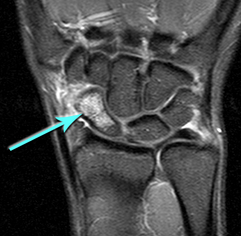

Unfortunately scaphoid fractures do not always show on an initial xray; they may not show up until the initial pain has settled down. The following patient's fracture did not show up on the original xrays taken in the A&E department. An MR scan shows the fracture clearly; the blue arrow points to the white area in the scaphoid that represents bruising in the bone. The subsequent xray confrims the presence of the fracture, albeit still very subtly (white arrows).